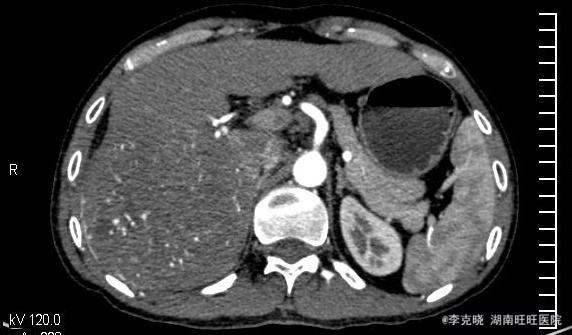

四测正常,皮肤巩膜无黄染,心肺部听诊未闻及杂音。腹平坦,未见胃肠型及蠕动波,无腹壁静脉曲张,全腹柔软,右侧肋缘深压痛,无反跳痛,肝肾无叩痛,肝肺浊音界清晰,肠鸣音正常。四肢活动自如,无水肿。 辅助检查提示:血常规、凝血常规基本正常,谷丙转氨酶278u/l,谷草转氨酶326u/l,AFP大于20000。上腹部CT增强提示:右肝巨大占位,平扫期呈低密度,动脉扫描时强化明显,静脉延迟象呈现低密度,结合病史考虑原发性肝癌可能,建议结合临床。

诊断:原发性肝癌(右肝巨块型)。治疗:考虑到患者的经济状况,结合肿瘤的影像学特点,经与患者充分沟通“以手术治疗为主的肝癌综合治疗思路”,最终患者选择先行TACE治疗。治疗后住院9天复查肝功能,转氨酶有下降趋势时,给予患者出院。一个半月后返院复查,转氨酶稍高,肿瘤内部碘油沉积满意,未见新生血管生成和新生病灶,建议患者继续观察、随访。